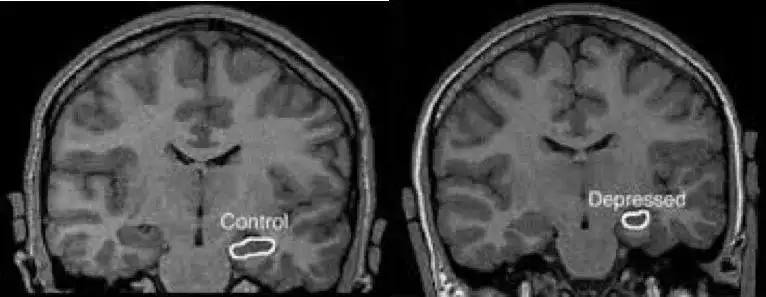

抑郁会造成海马体,丘脑,额叶和前额叶的萎缩,杏仁核的体积增加。这些体积的变化和抑郁的程度直接相关。